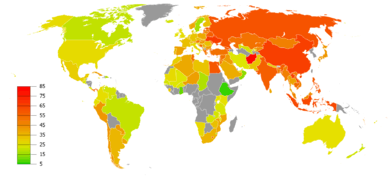

Smoking

The primary risk factor for COPD globally is tobacco smoking.[1] Of those who smoke about 20% will get COPD,[29] and of those who are lifelong smokers about half will get COPD.[30] In the United States and United Kingdom, of those with COPD, 80–95% are either current smokers or previously smoked.[29][31][32] The likelihood of developing COPD increases with the total smoke exposure.[33] Additionally, women are more susceptible to the harmful effects of smoke than men.[32] In non-smokers, secondhand smoke is the cause of about 20% of cases.[31] Other types of smoke, such as marijuana, cigar, and water pipe smoke, also confer a risk.[1] Water pipe smoke appears to be as harmful as smoking cigarettes.[34] Problems from marijuana smoke may only be with heavy use.[35] Women who smoke during pregnancy may increase the risk of COPD in their child.[1]